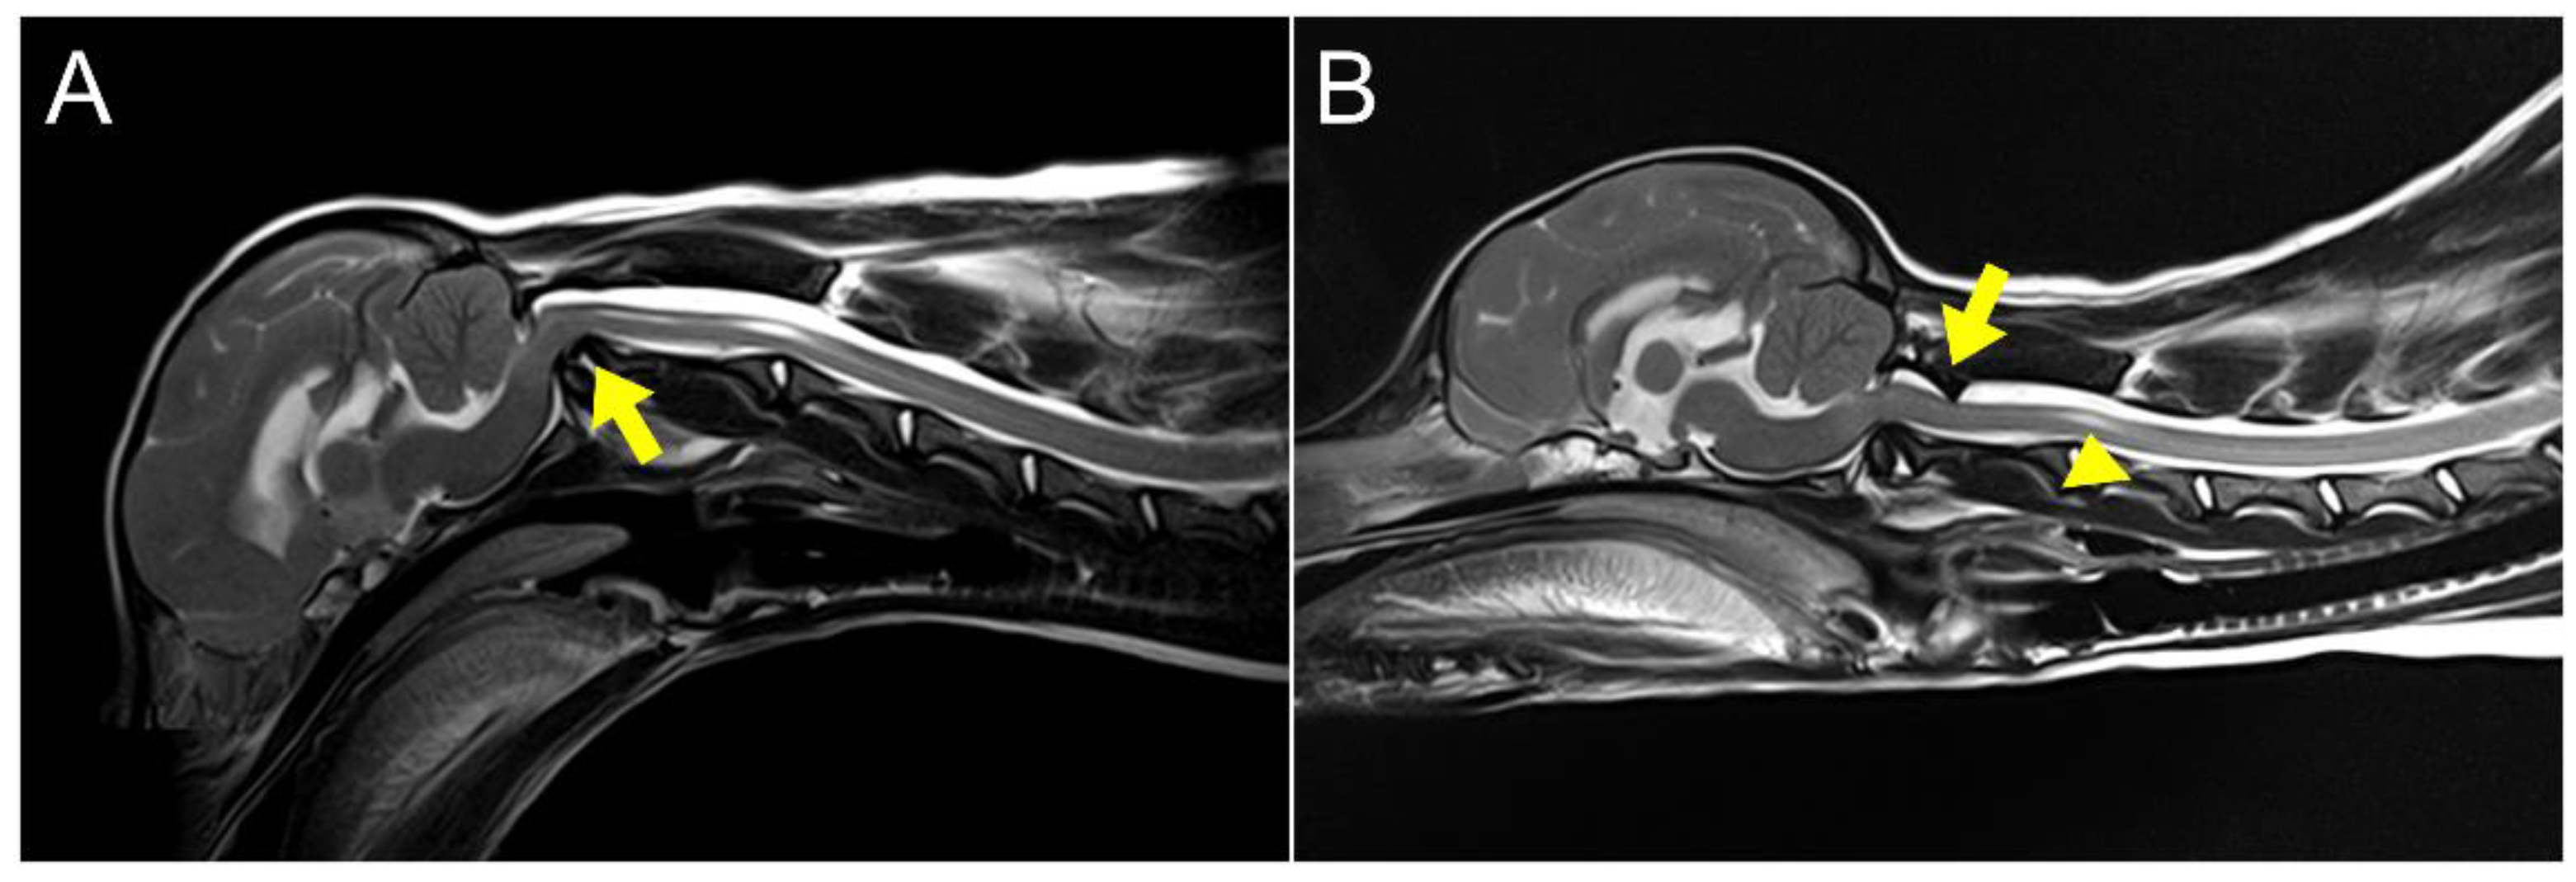

2. Case Description